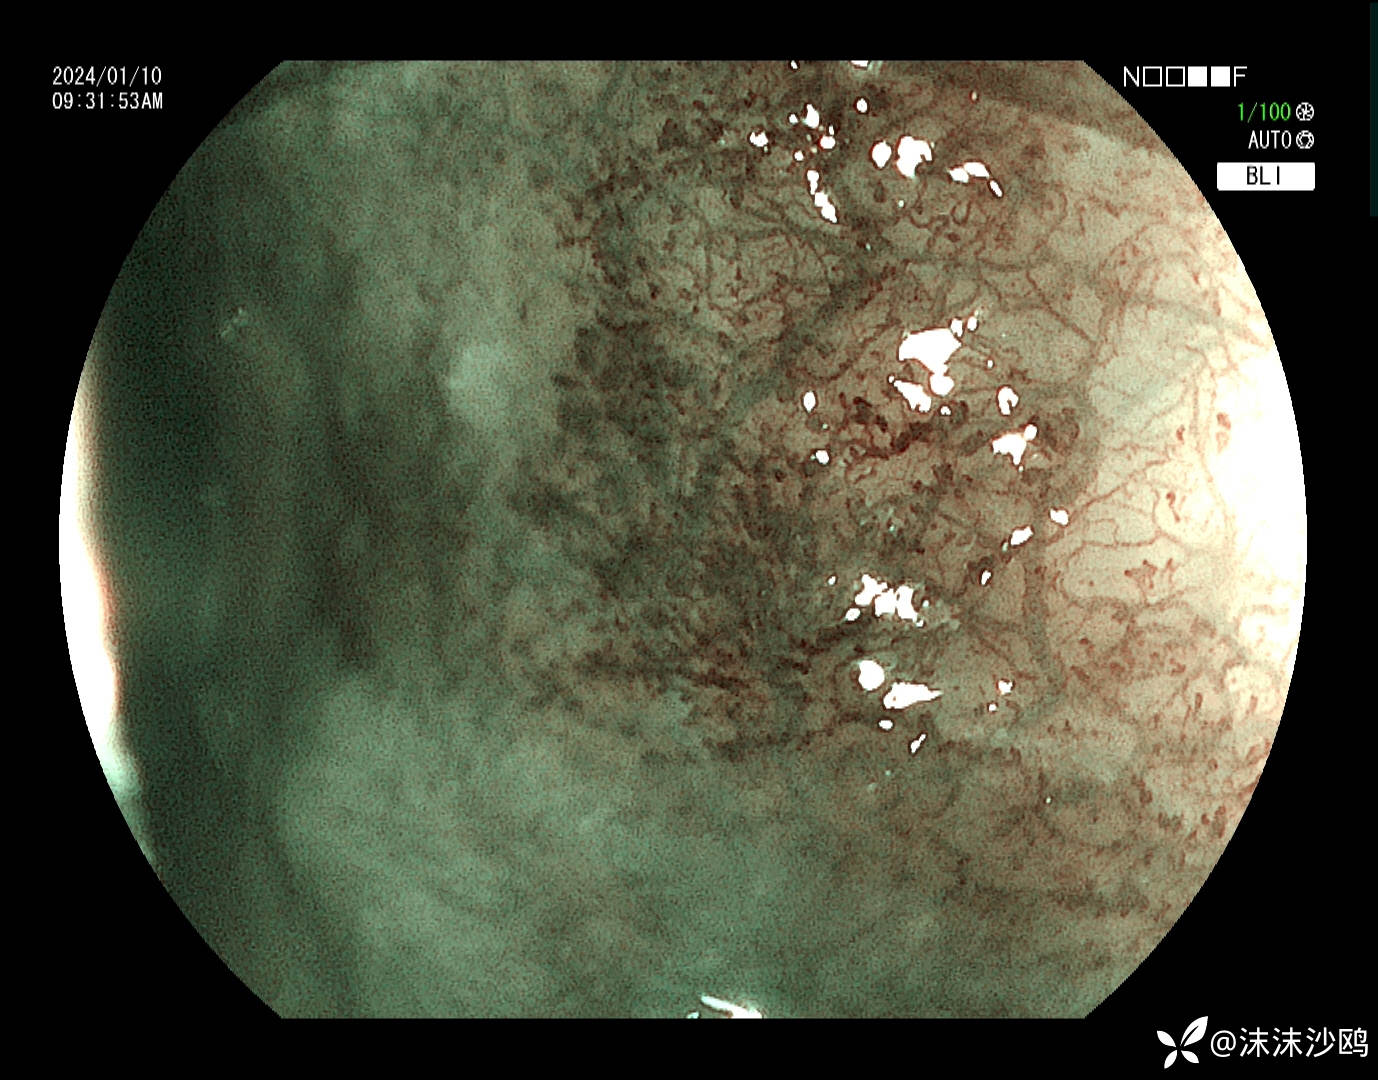

中年男子,自21年年初胃镜发现食管粘膜发红,今天是第五次复查胃镜。就是距门齿35cm一片状粘膜发红,表面比较平坦光滑,茶褐色改变。

今天的,做了放大,但我们没有碘染色剂,所有没做碘染。

后三次都是我做的,因为今天对比了病灶,感觉变化不明显,没有取病检。